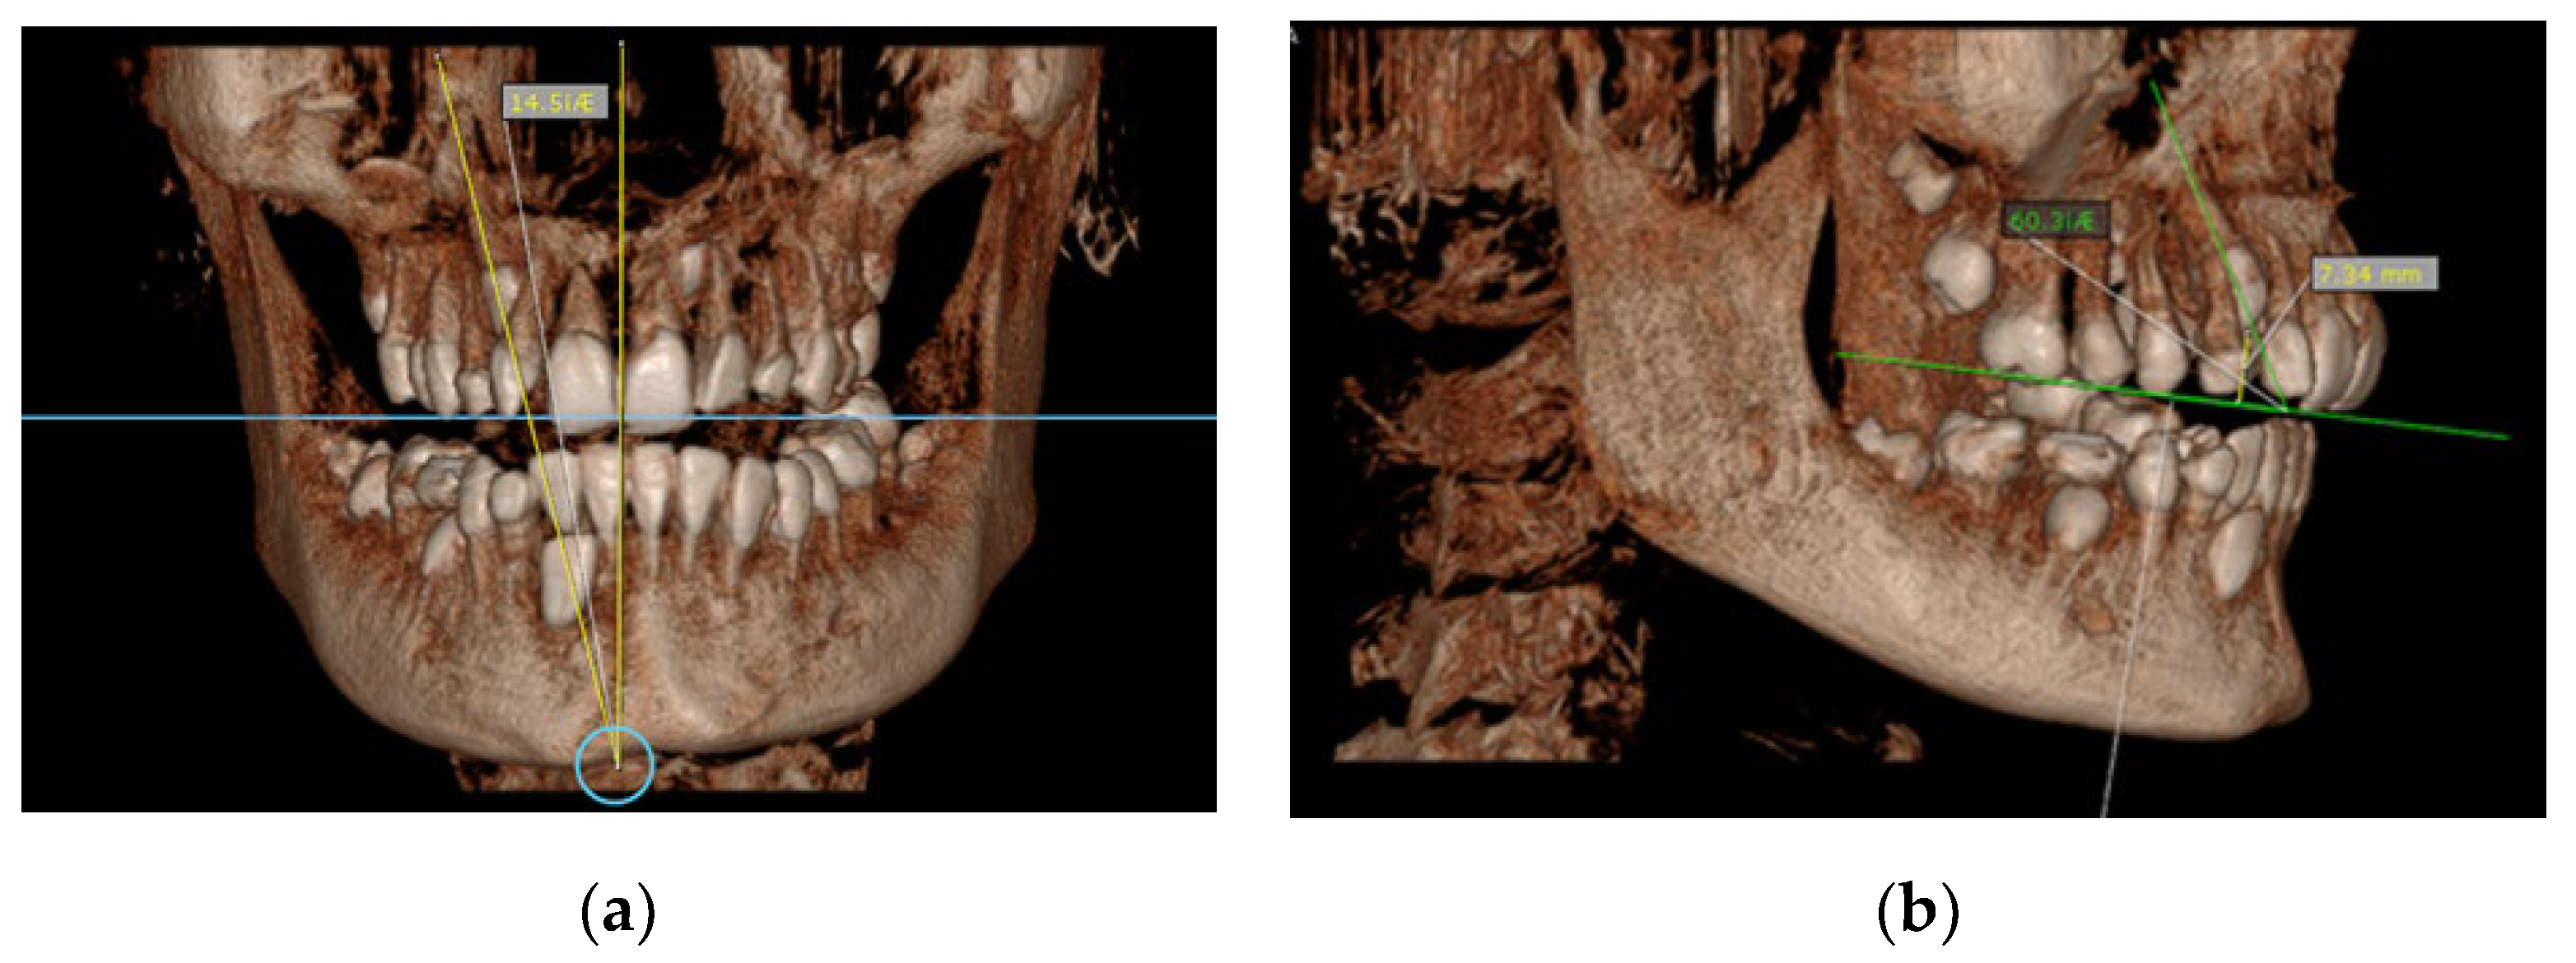

- Angle between the longitudinal axis of the impacted maxillary canine and the maxillary arch midline (measured on CBCT images in the coronal plan) (Figure 3a);

Figure 3. (a) Maxillary impacted canine angulation to the midline (measured on CBCT images in the coronal plan); (b) maxillary impacted canine angulation to the occlusal line and the distance canine cusp to occlusal line (measured on CBCT images in the sagittal plane).Figure 3. (a) Maxillary impacted canine angulation to the midline (measured on CBCT images in the coronal plan); (b) maxillary impacted canine angulation to the occlusal line and the distance canine cusp to occlusal line (measured on CBCT images in the sagittal plane).

Angle between the longitudinal axis of the impacted maxillary canine and the occlusal line (measured on CBCT images in the sagittal plane) (Figure 3b); - (9)